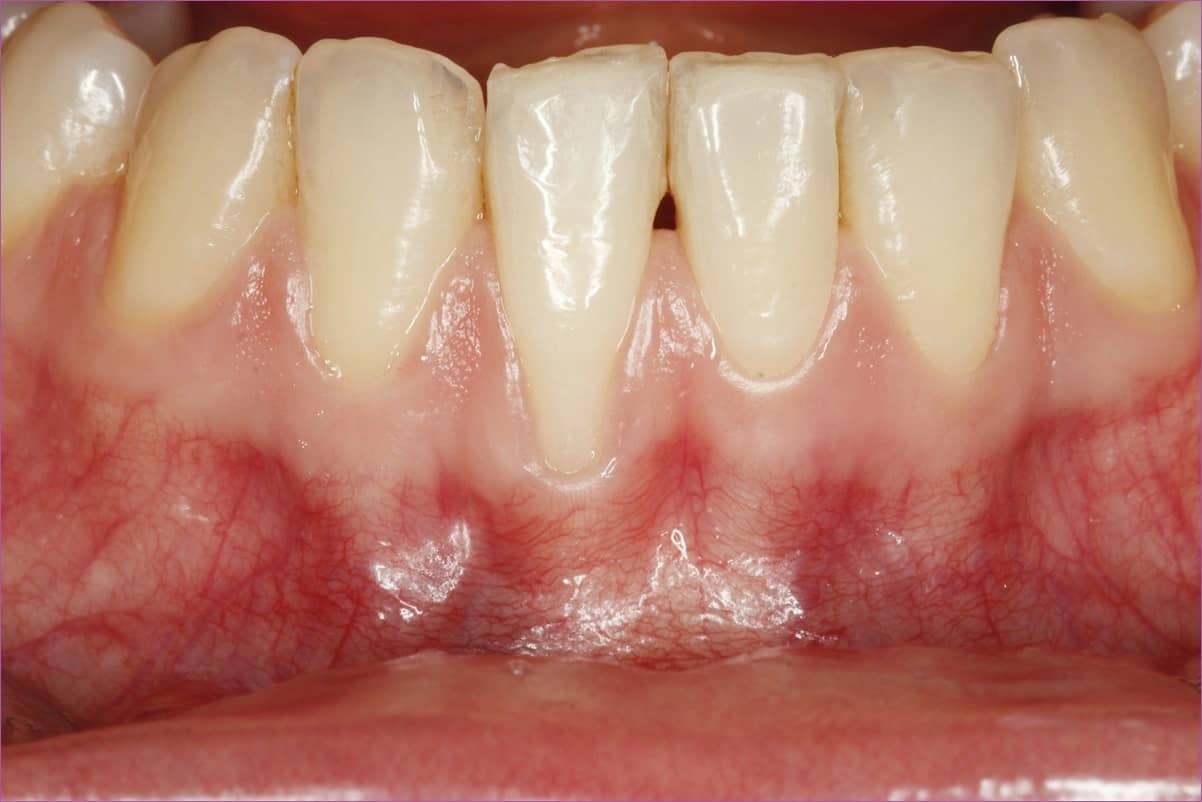

A fiatal hölgy azzal a panasszal érkezett dr. Orbán Kristóf parodontológuhoz, hogy a jobb alsó első metszőfogáról az íny visszahúzódott, a fog fogmosásnál, valamint hidegre-melegre érzékeny. Szájvizsgálat és radiológiai vizsgálat alapján a diagnózisa jobb alsó első kismetsző fognál Miller III. osztályba tartozó ínyrecesszió.

A terápia első lépése a dentálhigiénés kezelés volt, méghozzá több alkalommal is, egybekötve szájhigiénés instruálással, motiválással. A lehúzódott fogíny sikeres kezelésére ugyanis csak teljesen gyulladásmentes szöveti környezet, valamint tökéletes szájhigiéné esetén lehet számítani. Ellenkező esetben a műtét sikertelen lesz, az átültetett kötőszövet elhal.